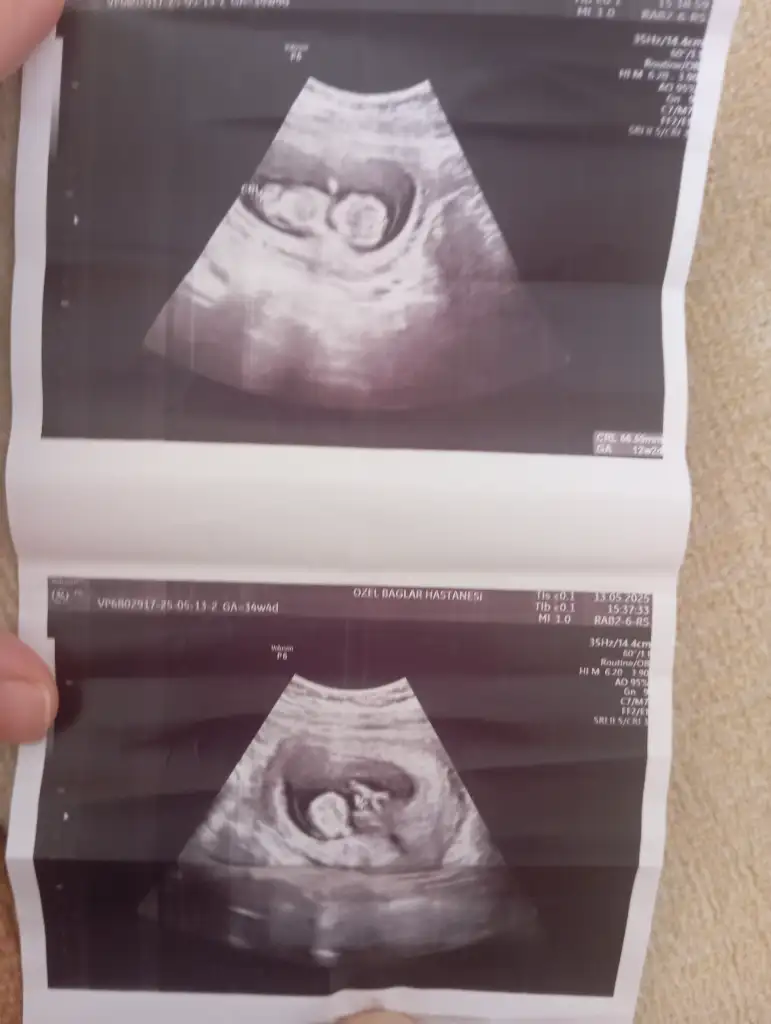

Kızlar bugün kontrolüm vardı şuan 12.haftamın içindeyim 2 li tarama yapıldı ama cinsiyetine erken olduğu için doktor bir şey demedi. Bir ay sonraya çağırdı gerçekten merak ediyorum tecrübeli olanlar varsa tahmin edebilir miBi de 2 gün geç döllenme olmuştu başta ama şuan 1 gün önden gidiyormuş belki işinize bana da yorum yaparmisiniz bende çok merak ediyorum

Bana da yorum yaparmisiniz bende çok merak ediyorumKızlar bugün kontrolüm vardı şuan 12.haftamın içindeyim 2 li tarama yapıldı ama cinsiyetine erken olduğu için doktor bir şey demedi. Bir ay sonraya çağırdı gerçekten merak ediyorum tecrübeli olanlar varsa tahmin edebilir miBi de 2 gün geç döllenme olmuştu başta ama şuan 1 gün önden gidiyormuş belki işinize yarar